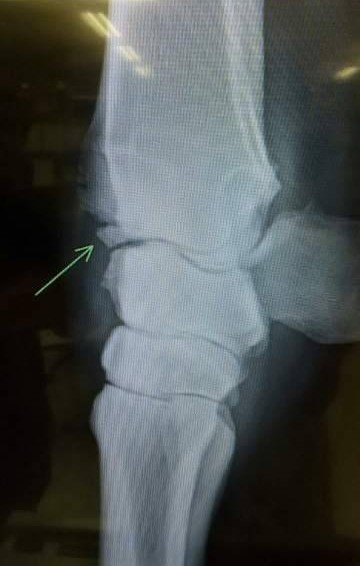

中央競馬ではデビュー以来コンスタントに出走してきましたが、2025年7月19日のレース中に左前橈骨遠位端剥離骨折を発症し、獣医師による診断の結果、全治6カ月との所見を受けました。今後については休養を挟んでの再起も検討いたしましたが、関係者一同で慎重に協議を重ねた結果、断腸の思いではありますが、今回のオークションに上場させていただく運びとなりました。現役続行および復帰に際しては剥離骨片の除去を推奨されておりますが、手術は行っておりません。また、骨折部周囲には骨膜の造成も確認されている旨、あらかじめご承知おきくださいますようお願いいたします。

※2025年7月19日の競走中に左前橈骨遠位端剥離骨折を発症。事故見舞金9号(競走中の事故により事故発生の日から6カ月以上出走できなくなった場合)の適用を受けています。